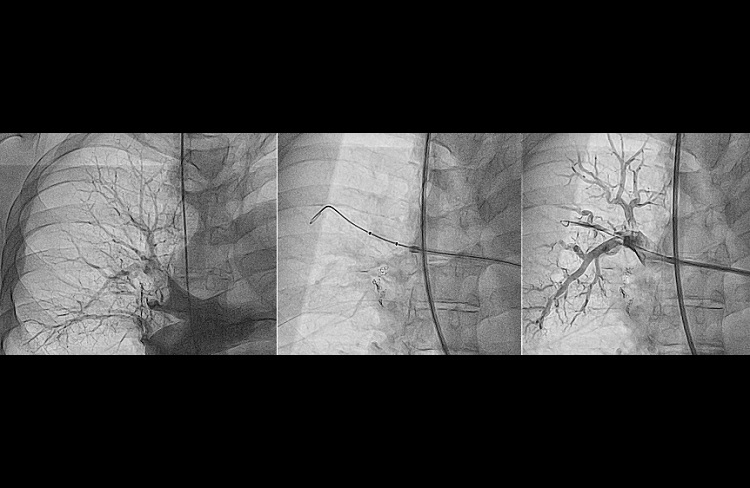

- diagnostyka ostrej zatorowości płucnej (angiografia tętnic płucnych);

- angioplastyki balonowe tętnic płucnych u chorych z nieoperacyjnym zakrzepowo zatorowym nadciśnieniem płucnym;

- Labyk A, Wretowski D, Zybinska-Oksiutowicz S, Furdyna A, Ciesielska K, Piotrowska-Kownacka D, Diduch OD, Lichodziejewska B, Biederman A, Pruszczyk P and Roik M. Balloon pulmonary angioplasty – efficient therapy of chronic thromboembolic pulmonary hypertension in the patient with advanced sarcoidosis – a case report. BMC Pulm Med. 2018;18:139.

- Roik M, Wretowski D, Labyk A, Irzyk K, Lichodziejewska B, Dzikowska-Diduch O, Piotrowska-Kownacka D and Pruszczyk P. Refined balloon pulmonary angioplasty-A therapeutic option in very elderly patients with chronic thromboembolic pulmonary hypertension. J Interv Cardiol. 2017;30:249-255.

- Roik M, Wretowski D, Labyk A, Kostrubiec M, Irzyk K, Dzikowska-Diduch O, Lichodziejewska B, Ciurzynski M, Kurnicka K, Golebiowski M and Pruszczyk P. Refined balloon pulmonary angioplasty driven by combined assessment of intra-arterial anatomy and physiology–Multimodal approach to treated lesions in patients with non-operable distal chronic thromboembolic pulmonary hypertension–Technique, safety and efficacy of 50 consecutive angioplasties. Int J Cardiol. 2016;203:228-35.

- Rzadkim odległym powikłaniem ostrej zatorowości płucnej jest nadciśnienie płucne o etologii zakrzepowo zatorowej (chronic thromboembolic pulmonary hypertension, CTEPH). W Klinice prowadzimy pełną diagnostykę chorych z podejrzeniem CTEPH, a tod 2014 wykonujemy plastyki balonowe tętnic płucnych u chorych z potwierdzonym CTEPH nie zakwalifikowanych do leczenia kardiochirurgicznego. Zabiegi wykonywane są z zastosowaniem nowoczesnych metod wewnątrznaczyniowego obrazowania (FFR/IVUS/OCT) co zwiększa bezpieczeństwo i skuteczność tych zabiegów.

- Plastyki balonowe tętnic płucnych u chorych z potwierdzonym zakrzepowo zatorowym nadciśnieniem płucnym z zastosowaniem nowoczesnych metod wewnątrznaczyniowego obrazowania (FFR/IVUS/OCT), co zwiększa bezpieczeństwo i skuteczność tych zabiegów.